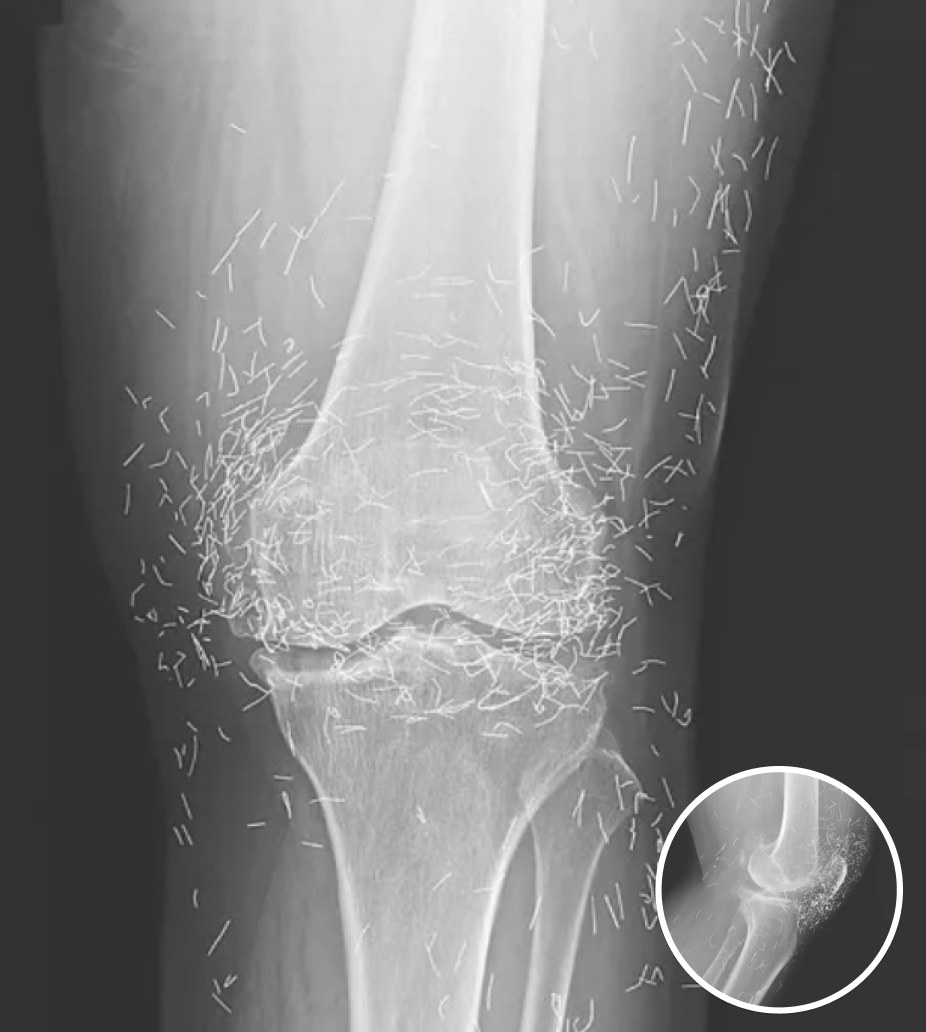

Doctors Stunned After Looking At This X-Ray Of Woman Suffering Joint Pain

A routine X-ray revealed an unexpected surprise when doctors examined the knees of a 65-year-old woman suffering from severe joint pain. What they found was nothing short of astonishing — hundreds of tiny gold needles embedded deep in her tissue.

A X-ray of the patient’s knee showing acupuncture needles embedded in the tissue, Photo Credit: Reddit

As for the South Korean woman, her case was recently documented in the New England Journal of Medicine. While the needles may have been intended to help, her X-rays tell a cautionary tale about the potential risks of extreme alternative therapies.